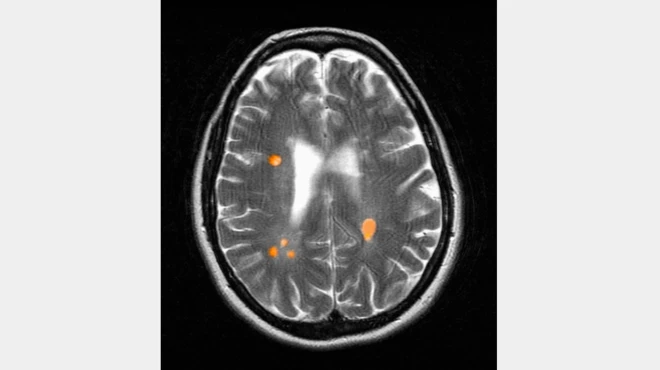

इसके अलावा टॉन्सिल में भी पथरी पाई जा सकती है.

गले में नीचे और पीछे की तरफ टॉन्सिल्स ग्रंथी होती है. ये लिम्फोइड टिशू के समूह होते हैं जो शरीर की रोग प्रतिरक्षा प्रणाली का हिस्सा होते हैं. लेकिन ये विडम्बना है कि उनमें बार-बार सूजन और संक्रमण हो सकता है.

टॉन्सिल्स में कैविटी यानी गड्ठे होते हैं जिन्हें क्रिप्ट्स कहा जाता है. कभी-कभी ये क्रिप्ट्स खाने और लार के टुकड़ों को रख सकते हैं, यही टॉन्सिल स्टोन या टॉन्सिलोलिथ होता है.

ये स्टोन अपेक्षाकृत नरम और कम पथरीले होते हैं, लेकिन वक्त के साथ ये भी सख्त हो सकते हैं और मुश्किल बन सकते हैं.

इस कारण व्यक्ति को सांस में दुर्गंध और बार-बार संक्रमण का सामना करना पड़ सकता है.